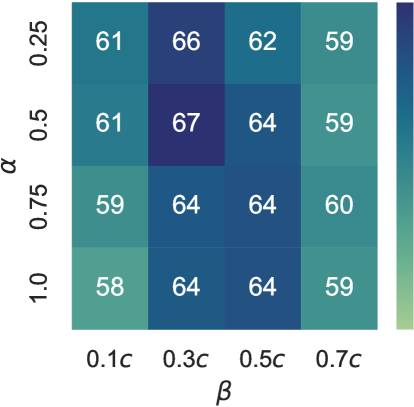

We performed an ablation study on the parameters and in our reward function. These parameters correspond to the late visit and true dismissal actions, respectively. Our experiment involved an evaluation on a grid, where and .

Given that the reward scale fluctuates with adjustments to these parameters, as indicated in Equations 13 and 12, we introduced the normalized score – recall-over-cost ratio as a metric for assessment of the results. For a comprehensive evaluation of accuracy, we utilized the BA score. The results are illustrated in Figure 7. Our findings revealed that the optimal parameter combination was and . This combination yielded a BA score of and a recall-over-cost ratio of , the highest scores among other combinations.